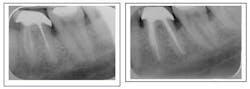

Separated instrument with incomplete fill and debridement